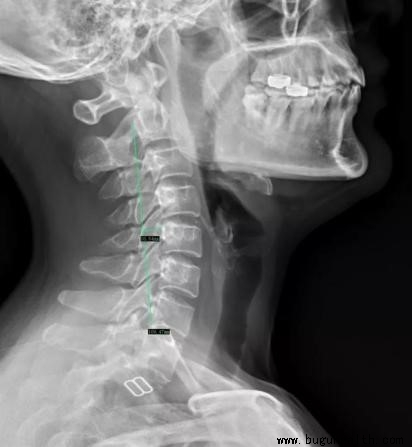

颈椎:Borden氏测量法,即自枢椎齿突后上缘到C7椎体后下缘画一直线,使椎体后缘与连线成一相应的自然弧,C5椎体后上缘为弧的顶点,弧最大垂直深度为(12±5)mm;当此数值 > 17mm 为曲度增大,< 7mm 为变直,< 0mm 为反弓。

布骨康复医疗中心